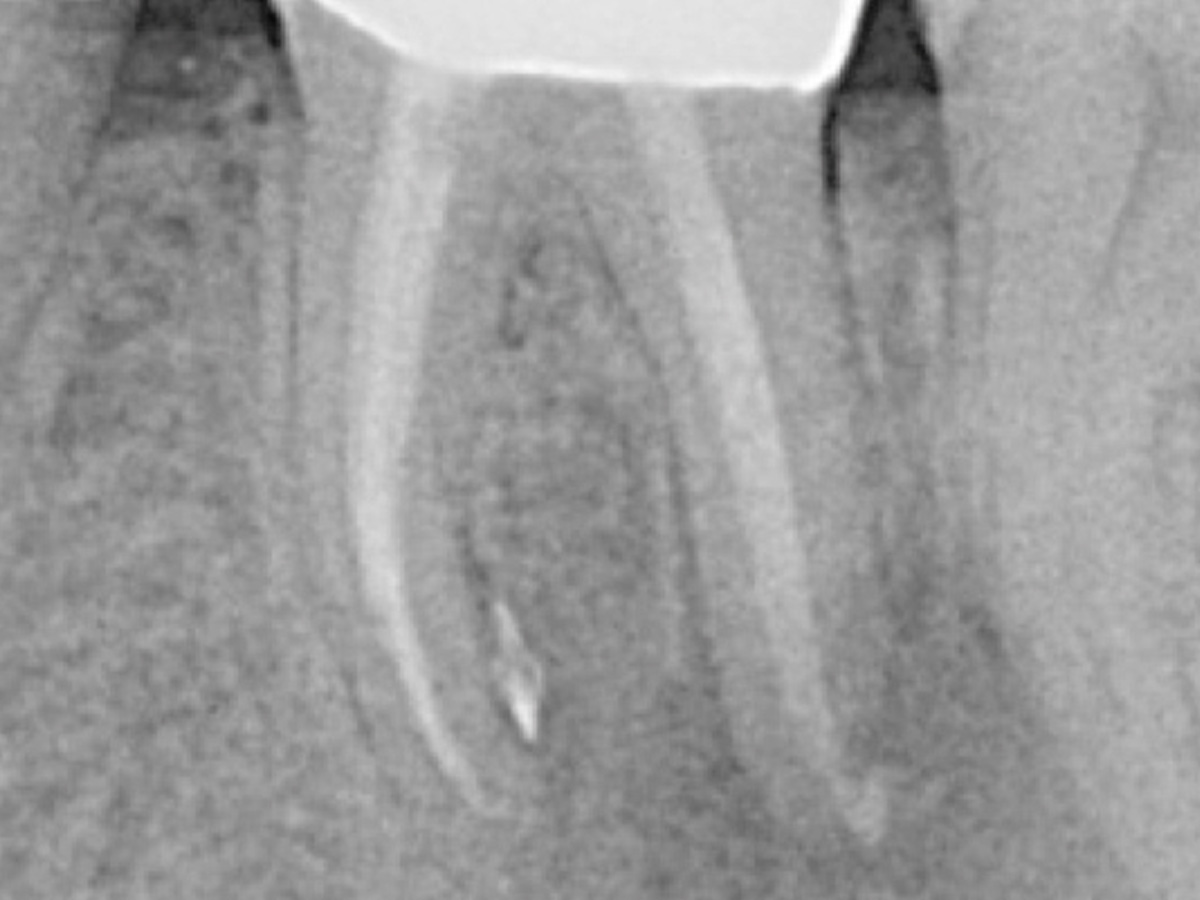

• Moderne endodontische Diagnostik

• 3D-basierte Planung der idealen endodontischen Zugangskavität und adäquaten minimalinvasiven Aufbereitung

• Techniken zur Bestimmung der idealen Arbeitslänge und Aufbereitungsgröße

• 3D-Obturation von Wurzelkanalsystemen